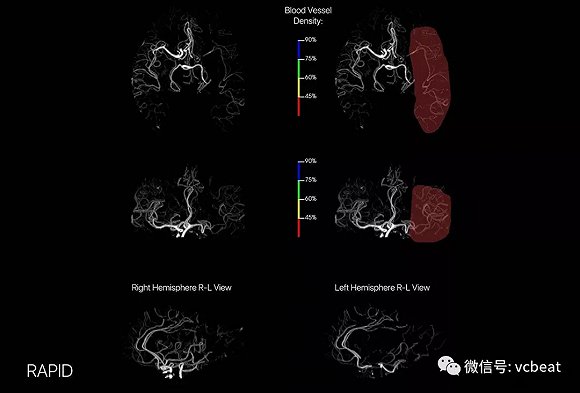

2、iSchemaView的RAPID CTA 3D成像平台

RAPID CTA影像

iSchemaView成像公司已获得FDA的最新产品RAPID CTA,这是一个用于计算机断层扫描血管造影(CTA)的3D成像平台。据该公司称,CTA扫描用于帮助临床医生观察患者在患者出现血栓的情况下的脑动脉。

RAPID ASPECTS基于临床验证的机器学习算法,自动生成标准化分数,使医生能够轻松地了解患者缺血性变化的程度,并确定血栓切除术(凝块去除)的可行性。

此外,RAPID ASPECTS提供清晰的大脑可视化,以便临床医生可以更好地仔细检查每个区域并确认自动评分。

该技术能够让医生全面了解大脑中的血管,医生可以在平台上以不同的角度旋转图像。CT图还具有四个彩色覆盖层,以便医生和护理人员可以看到大脑的哪些区域血管密度降低。

RAPID CTA图像映射可立即通过电子邮件提供给医生,以便在任何设备、PACS系统和Web浏览器上查看。这些影像提供了直观且易于解释的脑血管视图,帮助医生进行临床决策、分诊,便于社区医院和专家合作以及患者转诊。

目前全球有超过350个脑卒中中心使用RAPID,这些中心的日常使用每年产生超过50,000次扫描,预计2018年将有200个以上的系统投入使用,预计扫描计数每年接近100,000个。